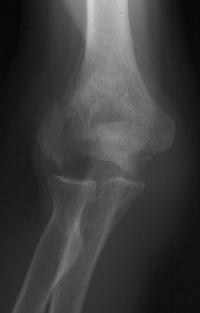

Screws were secured from the central articular component to the more proximal humeral cortices.

These provided biplanar fixation, eventually with two screws in each direction.

The lateral column was then secured with two cannulated screws.

The olecranon osteotomy was closed with a 6.5 mm lag screw and (belt and suspenders) tension band technique.

Anatomic reduction.